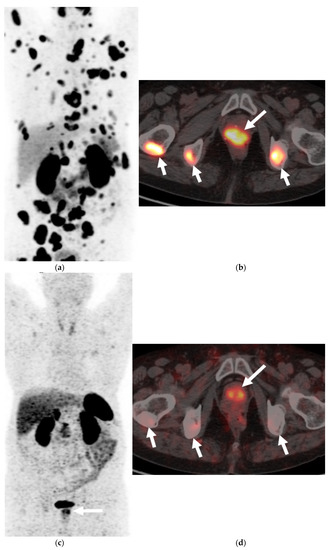

Figure 2. A 68-year-old man with palpable prostatic mass on rectal examination. Serum PSA was 0.3 ng/mL. Axial FDG-PET (a) and corresponding anatomic CT (b) of the PET-CT shows intensely hypermetabolic prostatic mass (long arrow) and pelvic bone metastases (short arrows). Axial lung window reformat of the CT chest (c) shows numerous small pulmonary nodules suspicious for metastases (arrows). Prostate biopsy showed high-grade carcinoma with neuroendocrine differentiation.- -

Most of the literature states that MDCT typically plays no role in the detection of PNEC and is not recommended for diagnosis. The only role of CT is for nodal staging, but it is also limited for this purpose, due to its inability to detect neoplastic architectural changes within less than 10 mm normal-sized lymph nodes (LNs) [30,31]. MDCT plays an important role in M staging for detection and restaging for bone and lung metastases in these cases (Figure 2 and Figure 3).

Multiparametric MRI (mpMRI) is now considered to be the standard imaging evaluation of choice when suspecting prostate cancer. Members of PI-RADS (version 2.1) steering committee recommend using 3T MRI scanners over 1.5T machines for prostatic evaluation, as it increases the signal-to-noise ratio (SNR), leading to an increase in both temporal and spatial resolution. If only 1.5T scanners are available or in the case of inherently low SNR sequences, such as DWI, they recommend the use of endorectal coil (ERC) which has the ability to increase SNR at any magnetic field strength [32]. Most tumors appear isointense to normal prostate tissue on T1-weighted sequences which serve as a baseline for the contrast-enhanced MRI, delineate the prostate outline, and can also demonstrate post-biopsy hemorrhage and periprostatic fat invasion. T2-weighted (T2W) sequences are used to evaluate prostatic zonal anatomy, primarily evaluate the transitional zone or central gland tumors, asses for seminal vesicle or nodal involvement, and detect extra-prostatic extension (EPE). Peripheral zone cancers usually demonstrate ill-defined T2 hypointense focal lesions with restricted diffusion and are primarily evaluated on ADC/DWI images (Figure 1). Transitional zone tumors appear hypointense with spiculated, ill-defined margins and smudgy appearance on T2W images. These lesions may also invade the urethral sphincter and anterior fibromuscular stroma [33,34]. While mpMRI is now considered the technique of choice for initial and local (T) tumor staging, PET/CT and PET/MRI have shown a great value in distant extraprostatic (N and M) staging (Figure 2), restaging after biomedical relapse, and response assessment after androgen deprivation therapy (ADR) [35,36,37,38]. The sensitivity, specificity, positive predictive value, and negative predictive value of multiparametric MRI for detection of EPE (Figure 3), were 48.7%, 73.9%, 35.9%, and 82.8%, respectively [39,40].

FDG is a glucose analog and its uptake reflects the tissue glucose metabolism. Due to increased uptake in neoplasms, resulting from the increased metabolic activity of the tumor cells, it is the mainstay of molecular imaging and the most commonly used PET tracer to evaluate tumors [47,48]. It has a limited value when it comes to prostate cancer as a result of low glucose metabolism and the use of non-glucose metabolic pathways, e.g., fructose and fatty acid metabolism in the tumor [49,50]. However, Spratt et al. demonstrated that 18FDG PET has clinical utility in the metastatic evaluation of NEPC (Figure 2) and this may be due to high glucose metabolism of the usually high-grade neuroendocrine cancers seen in prostate. FDG PET findings can also serve as prognostic marker in cases of metastatic NEPC. When stratified by the median survival from NEPC diagnosis, patients who survived <2.2 versus ≥2.2 years, had more PET avid bone and soft tissue lesions and higher average SUVmax of bone and soft tissue lesions [51,52]. Some low-grade neuroendocrine tumors may not be intensely FDG-avid and rather may be more intensely avid on 68 Gallium DOTATATE PET, as shown with gastroenteropancreatic neuroendocrine neoplasms [53].

There is no core difference in staging between prostatic adenocarcinoma and NEPCs. The TNM staging system, developed by the American Joint Committee on Cancer (AJCC), is the most commonly used staging method to assess the tumor status (T), lymph nodes (N), and metastasis (M) [70]. Unlike prostatic adenocarcinoma, clinical tumor stage 1 is uncommonly seen in cases with NEPC and they usually present with higher stages, with more visceral and nodal metastases with predominantly lytic bone lesions. Hence, NEPC is clinically suspected when a prostate cancer is seen with absent or a low/moderate rise in PSA, presents at advanced stage, or has a predominance of visceral and/or bone metastatic disease (Figure 2). In addition, NEPC is also suspected when the prostate cancer becomes unresponsive to ADT with rapid disease worsening (Figure 3 and Figure 4) [68,69]. Paraneoplastic syndrome is also a potential distinguishing feature for NEPCs, especially SCNC, with Cushing’s syndrome being the most common manifestation [71,72]. Currently, the reference standard for the diagnosis of NEPCs is pathologic examination showing the above microscopic features, plus the presence of neuroendocrine IHC markers, e.g., NSE, SYN, and CgA [16,73].